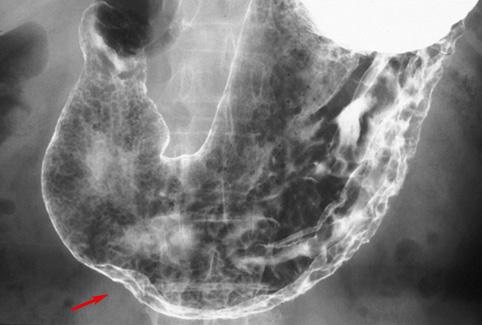

疾病(病理主体)的分类寄生虫疾患/异尖线虫

部位(按器官分)胃(部位)/前庭

检查方法X线

肿瘤最大直径15~19